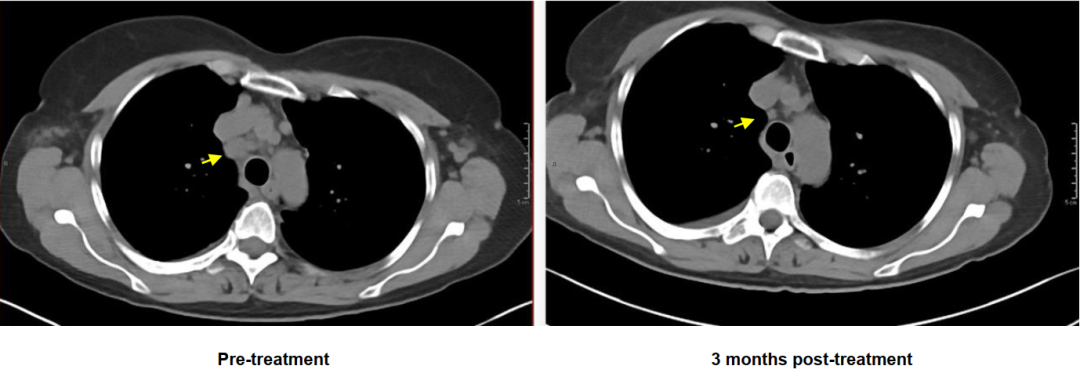

其中一位部分缓解患者三个月前后的治疗效果图

研究人员再次选取了一位符合条件的48岁晚期乳腺癌患者,使用她的外周血淋巴细胞,来制作靶向P53突变的TCR-T细胞。在接受治疗前,这位患者的病情十分危重,双侧乳房都被真菌样肿物侵蚀,还有左侧胸腔积液和心包填塞。

好在TCR-T的疗效令人惊喜。治疗后6周和14周时,靶病灶的肿瘤体积分别减少了37%和55%,心包、胸壁和皮下的肿瘤转移明显减少,所有可见的皮肤病变都在治疗后60天完全消失。